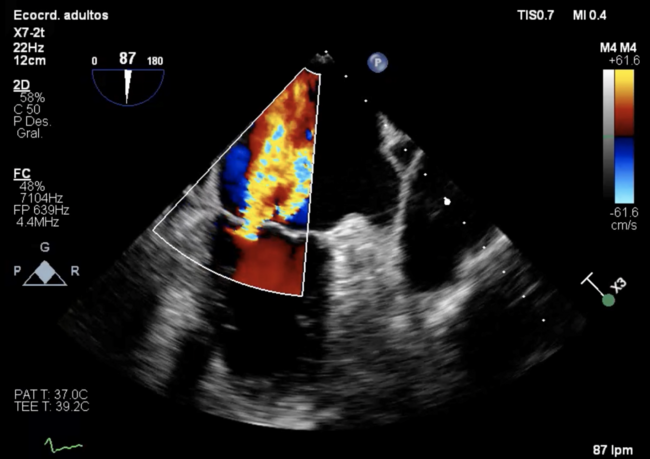

Mitraclip, Amplatzer, and TricValve Devices in a High-Risk Patient With Polyvalvular Disease

Video supplement to "Three Devices on One" by Gonzálvez-García, et al. (February 2023 Clinical Images).

To the best of our knowledge, this case represents the first patient with Mitraclip, Amplatzer, and TricValve devices with a profound clinical improvement and long-term follow-up. In addition, this case illustrates how the treatment of high-risk patients with polyvalvular disease has changed in the last few years.